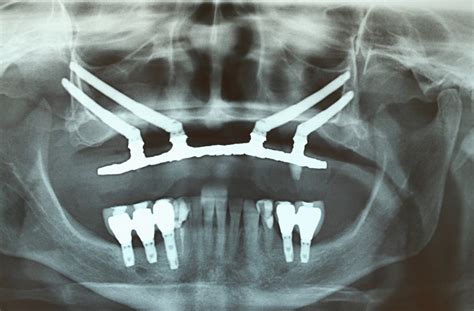

Implantes zigomáticos

Los implantes zigomáticos ofrecen solución a pacientes con atrofia ósea (poco hueso en el maxilar), con una rehabilitación rápida, predecible, eficaz y sin necesidad de colocar injertos óseos. Técnica que se recomienda especialmente para aquellos pacientes que los tratamientos con implantes convencionales e injertos óseos les han resultado un fracaso.